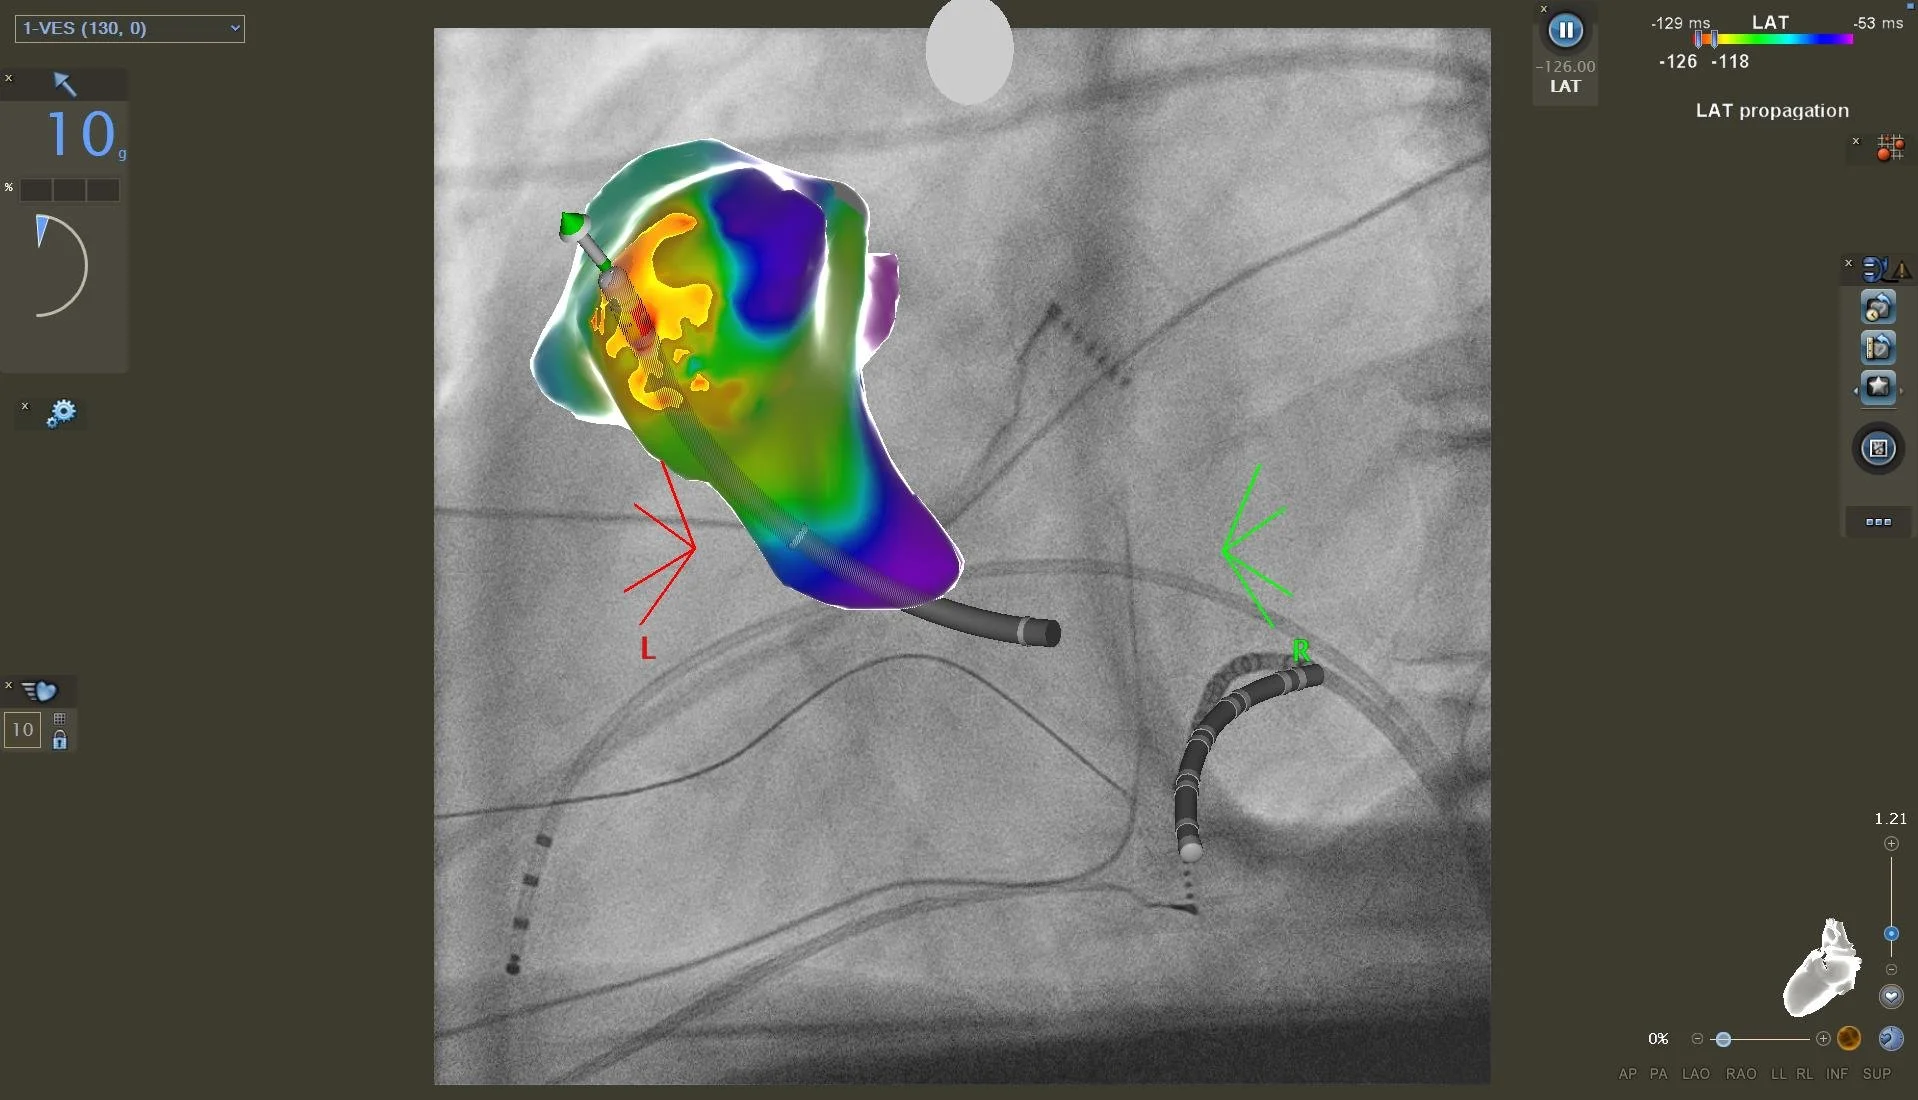

3D Navigation einer VES Extrasystolie

Im Rahmen spezieller elektrischer Herzkatheteruntersuchungen können wir die Reizleitungseigenschaften des Herzens untersuchen - hierzu werden über die Leiste elektrische Herzkatheter am Herzen positioniert und über Provokationsmanöver die Herzströme vermessen. Auftretende Rhythmusstörungen können unter Verwendung eines hochmodernen 3D-Navigationssystems mit Röntgen-Bildfusion genau kartiert werden, und können prinzipiell auch Strahlen- und Kontrastmittelfrei erfolgen. In gleicher Sitzung kann dann auch die Verödung der Herzrhythmusstörung erfolgen.